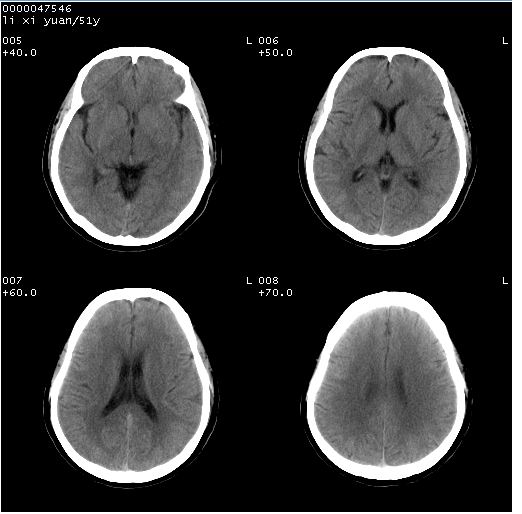

以下是引用余辉在2008-4-27 14:02:00的发言:[br]病灶位于中央沟前方?位于额叶?高密度灶,灶周水肿不明显,病灶似沿脑沟走行,强化明显,局部层面呈现环状强化,考虑1脑表面血管性疾病,如血管瘤,血管扩张,灶内血栓形成,其次考虑肿瘤如脑膜瘤、转移瘤,胶母等

以下是引用形影不离在2008-4-27 14:13:00的发言:[br]考虑胶质瘤可能性大,不排除慢性炎性肉芽肿。建议mri检查。